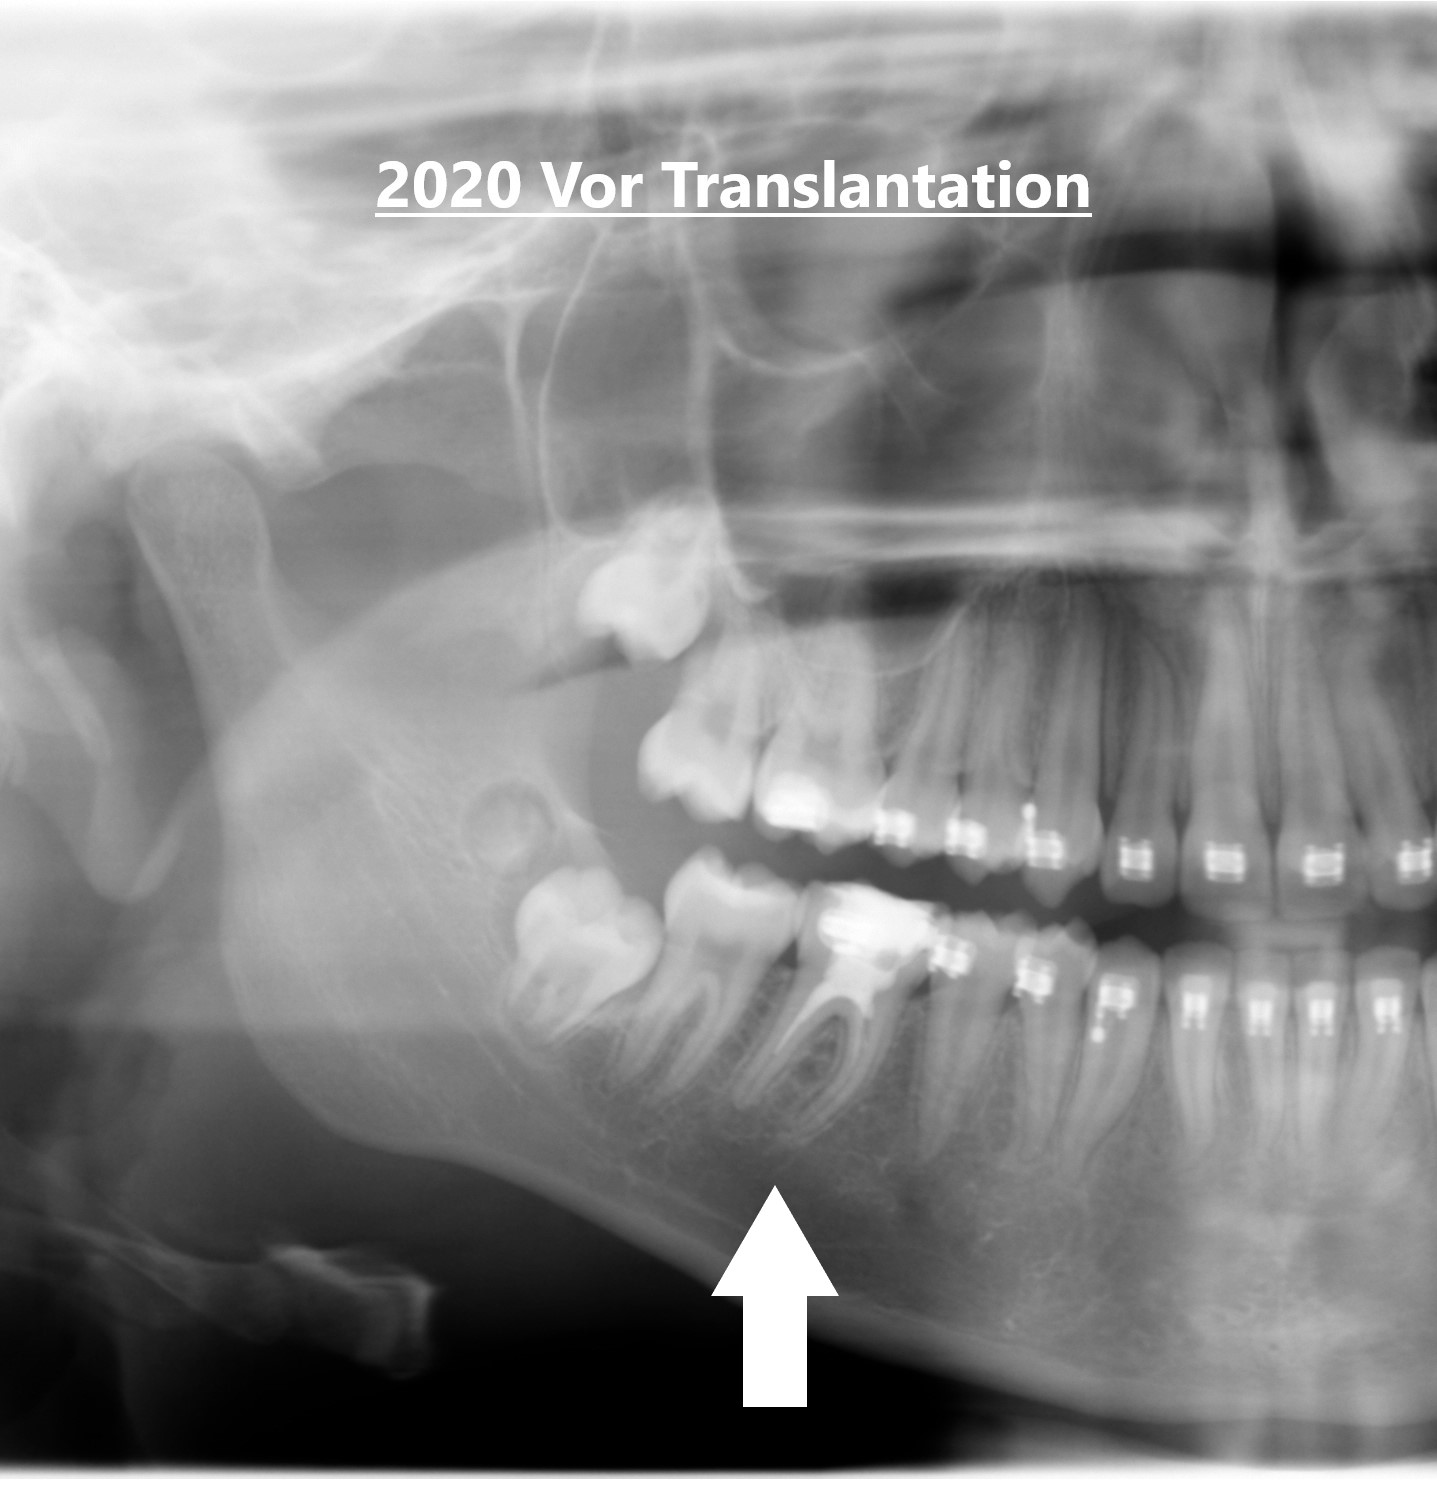

Erfolgreiche Weisheitszahn-Transplantation Köln

Erfolgreiche Weisheitszahn-Transplantation im Haus der Zahngesundheit Köln – kranker Backenzahn wurde durch eigenen Weisheitszahn ersetzt, vital und funktionell eingewachsen.

Transplantation eigener Weisheitszähne – natürlich, biologisch & erfolgreich Weisheitszahn-Transplantation Köln – Natürlich ersetzen statt implantieren Wenn ein Backenzahn erkrankt oder nicht mehr zu erhalten ist, bedeutet das heute nicht zwangsläufig den Verlust der Kaufunktion.Statt eines Implantats bietet die Weisheitszahn-Transplantation Köln eine natürliche und biologische Alternative.Dabei nutzen wir den eigenen Weisheitszahn als Ersatz – eine schonende Erfolgreiche Weisheitszahn-Transplantation Köln